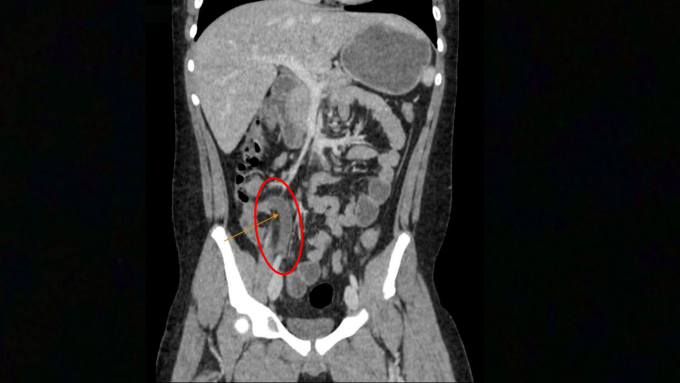

Kết quả xét nghiệm máu của bé Hưng tại Phòng khám Đa khoa Tâm Anh Quận 7 ghi nhận chỉ số bạch cầu 22.74 K/ul (bình thường dưới 10 K/ul), CRP tăng 4 lần so với bình thường cho thấy viêm nhiễm cấp tính nặng. Chụp CT-Scan cho thấy ruột thừa bé Hưng đường kính 12 mm (trên 6 mm là viêm), kèm sỏi phân 8 mm gây bít tắc lòng ruột thừa. Sỏi phân làm tăng áp lực trong ruột thừa, chèn ép mạch máu, dẫn đến viêm hoại tử, vỡ ruột thừa trong thời gian ngắn, phải phẫu thuật cấp cứu.

Hình ảnh CT cho thấy viêm ruột thừa kèm sỏi phân. Ảnh: Phòng khám Đa khoa Tâm Anh Quận 7